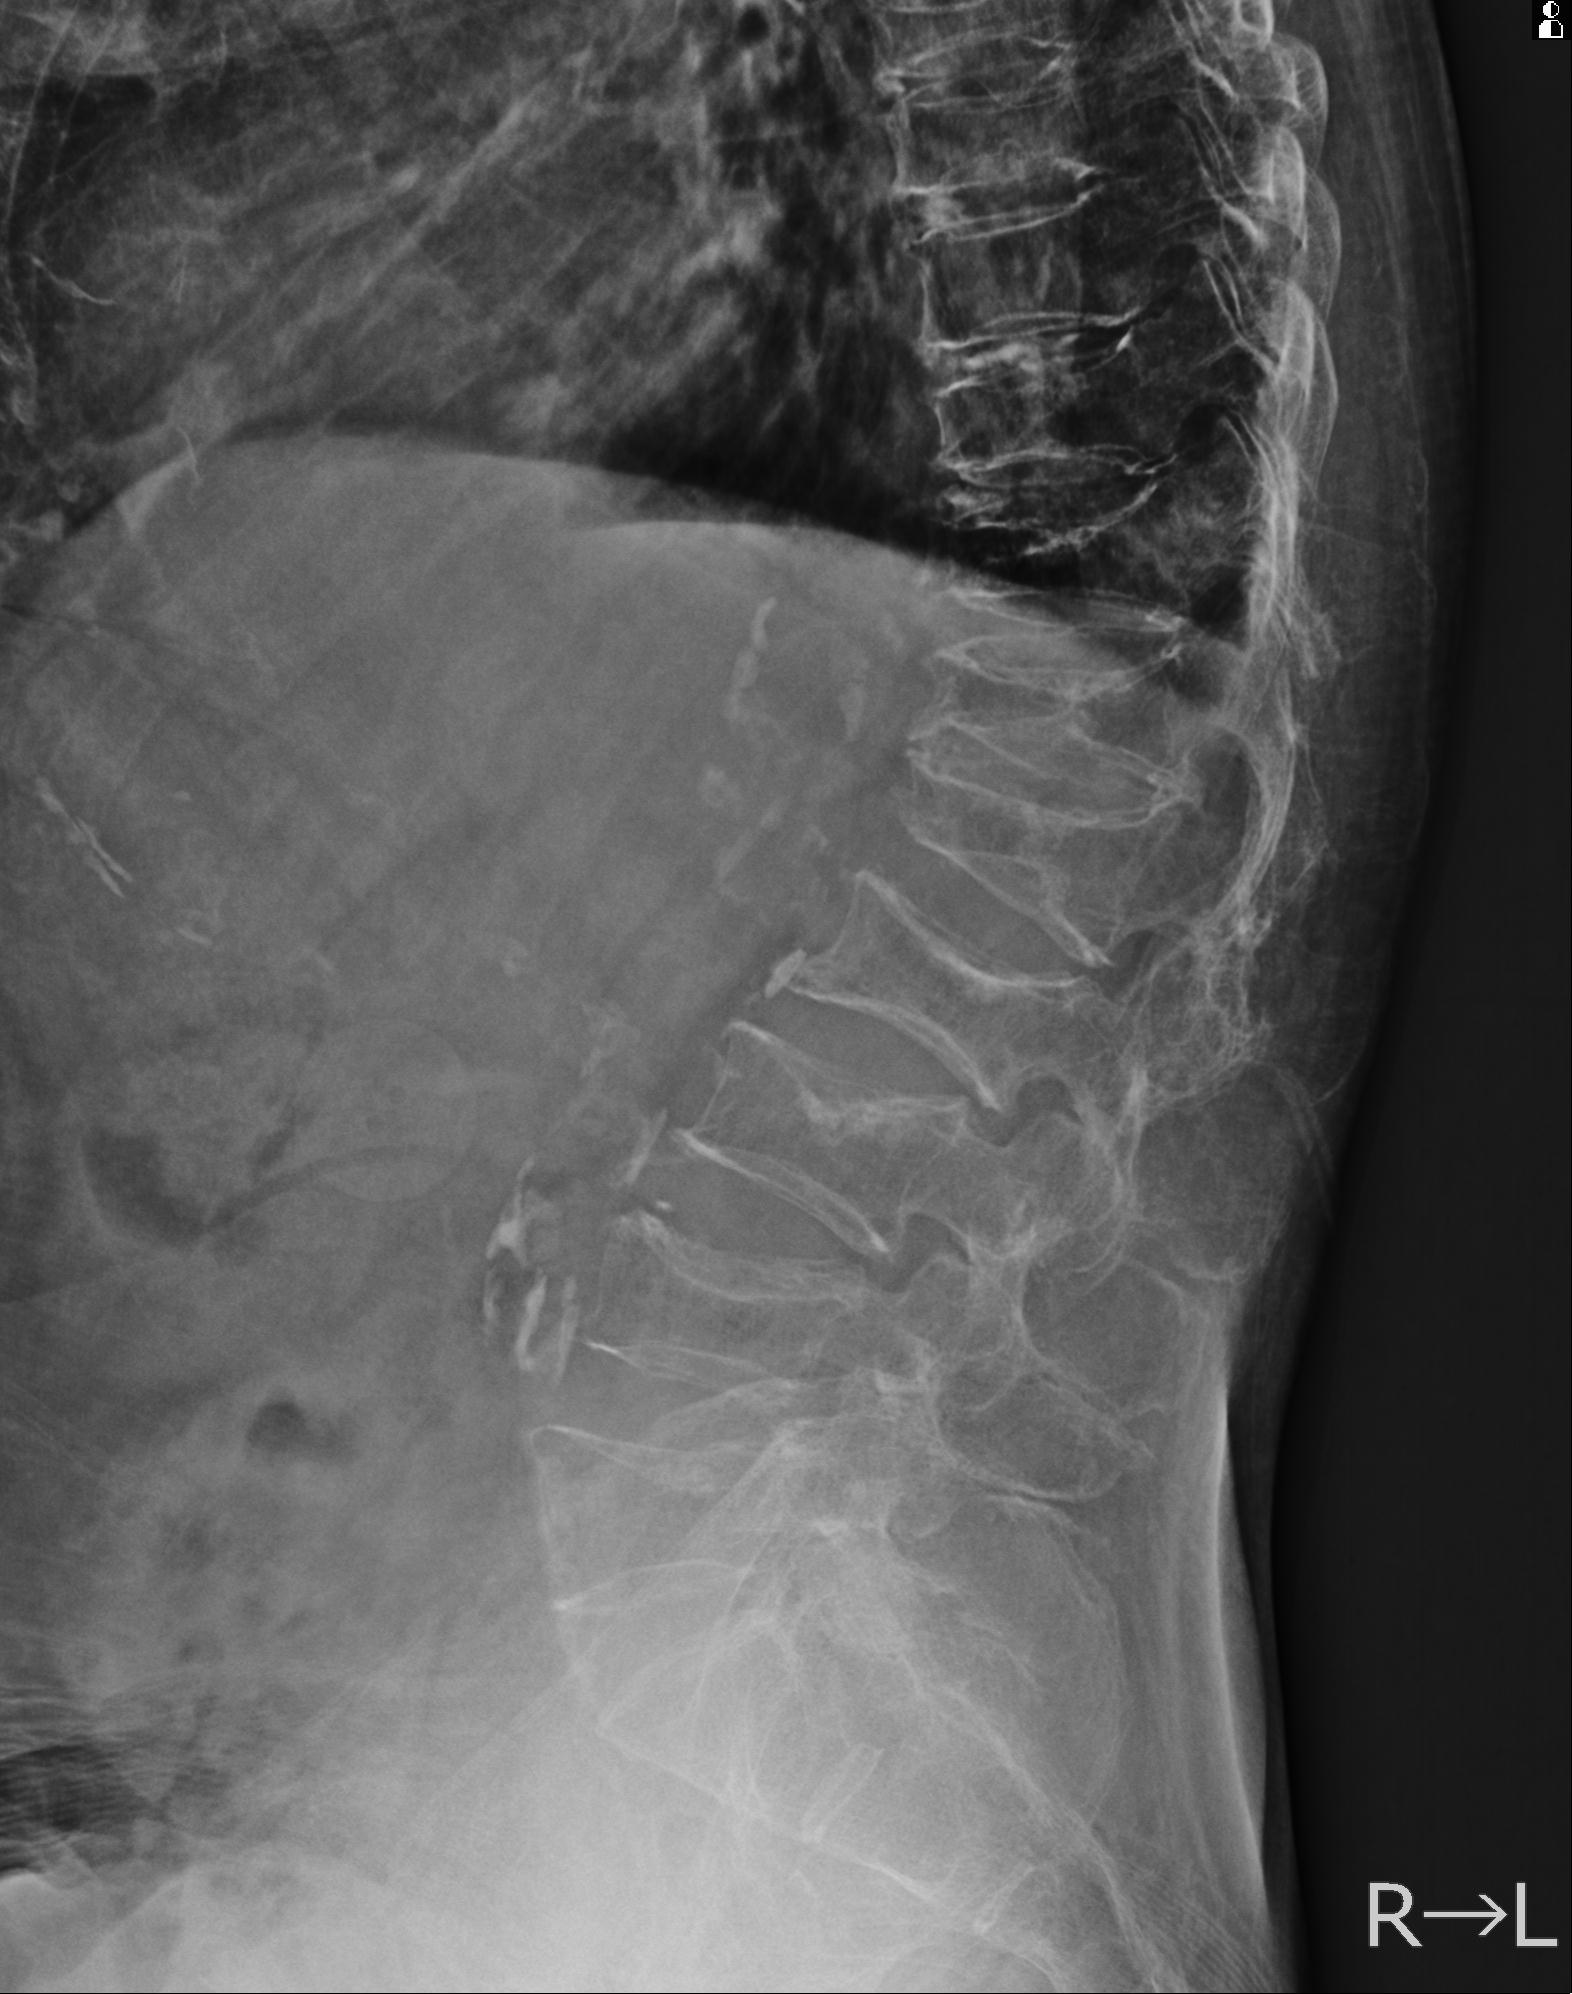

102916 2/1 と 3/22 腰椎 2R 74歳女性 LIFX